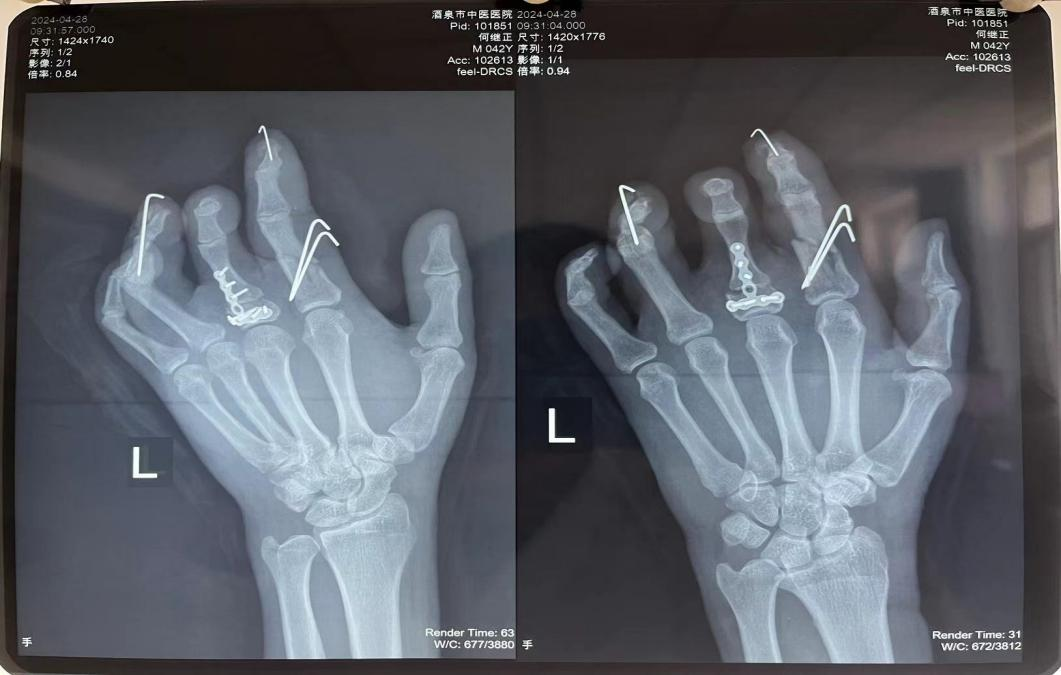

日前,我院手足顯微外科為一名“手指異位再植”的患者行“游離第二足趾再造術(shù)”,經(jīng)過(guò)手足顯微外科醫(yī)護(hù)團(tuán)隊(duì)的精心治療,現(xiàn)患者臨床治愈出院?;颊邽榍筮M(jìn)一步康復(fù)功能鍛煉,遂前往我院針灸康復(fù)科治療。 該患者入院時(shí)左手腫脹,關(guān)節(jié)、肌腱粘連,被動(dòng)活動(dòng)疼痛明顯,入院后針灸康復(fù)科康復(fù)小組為患者制定了詳細(xì)的康復(fù)方案。一方面治療師對(duì)患者左手的各關(guān)節(jié)進(jìn)行了松解、被動(dòng)屈伸等治療,另一方面配合中藥、中醫(yī)理療等有效緩解患者術(shù)后的腫痛。經(jīng)過(guò)幾天的系統(tǒng)治療,患者左腕關(guān)節(jié)可自主背伸、掌屈,左手示指、小指、環(huán)指掌指關(guān)節(jié)可被動(dòng)伸直,腫脹疼痛明顯減輕。 對(duì)于手外傷術(shù)后的患者來(lái)說(shuō),手術(shù)的成功固然重要,但是手功能的康復(fù)鍛煉也必不可少!此次我院針灸康復(fù)科通過(guò)積極與手足顯微外科的交流協(xié)作,通過(guò)詳細(xì)了解患者病情及手術(shù)方式,制定了專業(yè)的個(gè)體化康復(fù)方案,不僅取得了良好的治療效果,也為我院多學(xué)科間的協(xié)作診療提供了范例。